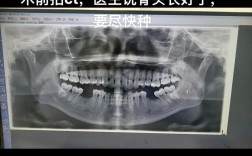

- 种植体周围X线片显示骨吸收: 这是诊断和评估严重程度的关键,可以看到种植体周围牙槽骨高度降低,形成“骨陷窝”。